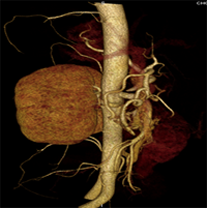

目前臨床對于16層CT的認可主要集中在三維成像領域上的突破.在16層CT的產品平臺上,常規(guī)掃描就能實現(xiàn)滿足三維成像的要求,因此16層也被稱為三維CT,三維成像給臨床診斷帶來了更精確更豐富的診斷信息,我們以臨床為例:

如上圖所示,相鄰的三張軸位圖像未見明顯異常,根據(jù)傳統(tǒng)軸位圖像很難得到準確的臨床診斷。

同一病人利用容積數(shù)據(jù)進行三維處理后,高品質MPR和三維圖像上則清晰顯示了縱向排列的腹腔干與腸系膜上動脈相鄰近,血管發(fā)生變 異,近端血管閉塞,為臨床提供了精確的診斷信息。

從上面的例子可以看到,能否為臨床提供高品質的三維影像成為了16層CT的核心價值,而東芝新一代的 全景三維16層CT擁有最為  先進的3項核心技術,在16層核心價值上的表現(xiàn)自然值得期待。

TCOT+----------全景三維重建算法

三維影像最核心的價值在于高精度的重現(xiàn)人體真實的三維結構,而以往的CT在采集中受到錐形線束偽影的影像視野邊緣的數(shù)據(jù)不足,因而傳統(tǒng)的重建算法獲得三維圖像易出現(xiàn)邊緣失真,進而影響臨床診斷。

東芝專利的TCOT+算法基于AQUILION ONE動態(tài)容積CT的全景重建技術,最大限度的抑制了錐形線束偽影對三維圖像的影響,使邊緣數(shù)據(jù)量增大了25%,從而實現(xiàn)。

全新三維模板

全景三維CT內置全新三維模板系統(tǒng),臨床只需要選擇病人容積數(shù)據(jù),點擊相應模板系統(tǒng)就能自動生成臨床需要的三維影像。全景三維CT還具備獨特的多組織疊加和MPR融合功能,可以根據(jù)不同組織密度進行提取和標記后將圖像按照臨床需求進行融合顯示,也可以將MPR和三維圖像融合同時提供二維和三維結構的一體化圖像,這些先進的三維影像處理方式能夠為臨床提供更為豐富的診斷信息和更加直觀的高品質三維影像。